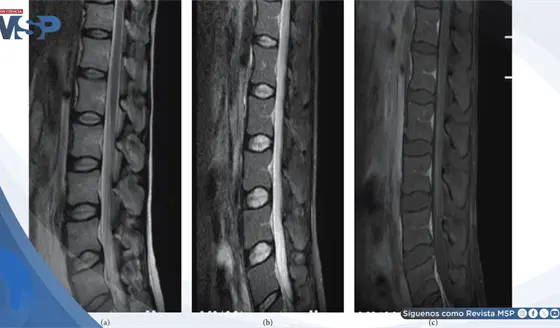

Una ecografía abdominal mostró una masa lobulada de más de 10 cm en la región epigástrica. Para caracterizarla mejor, se realizó una tomografía computarizada (TC), la cual confirmó la presencia de dos grandes masas y una importante linfadenopatía mesentérica (ganglios linfáticos agrandados en el abdomen).

Para obtener un diagnóstico definitivo, era necesario analizar el tejido. Se realizó una biopsia con aguja gruesa de los ganglios linfáticos abdominales. Bajo el microscopio, los patólogos observaron un panorama sorprendente: en lugar de células cancerosas, la lesión estaba compuesta predominantemente por células fusiformes (células alargadas) dispuestas en patrones específicos, mezcladas con histiocitos espumosos y algunos granulomas.

Este patrón podía simular un tumor, pero la atipia celular era mínima. Los estudios de inmunohistoquímica, una técnica que usa anticuerpos para identificar proteínas en las células, arrojaron un resultado crucial: las células eran positivas para CD68 (un marcador de células del sistema inmune llamadas histiocitos) y para S-100.

Más importante aún, la tinción especial para bacilos ácido-alcohol resistentes (BAAR) reveló la presencia de micobacterias en el tejido.

La combinación de todos estos hallazgos –la imagen de masa tumoral, la histología con células fusiformes de origen histiocítico y la confirmación de la infección micobacteriana– llevó al diagnóstico final: Pseudotumor de Células Fusiformes Micobacteriano (MSP, por sus siglas en inglés).